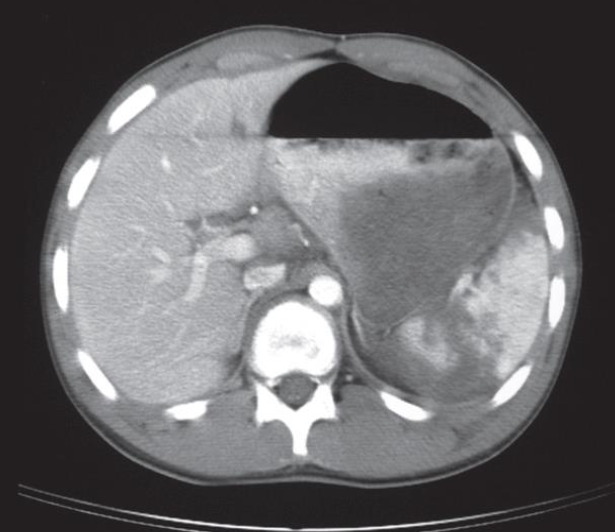

A. Imaging study? CT angiogram (3D)

B. What is the most probable diagnosis; Aortic aneurysm.